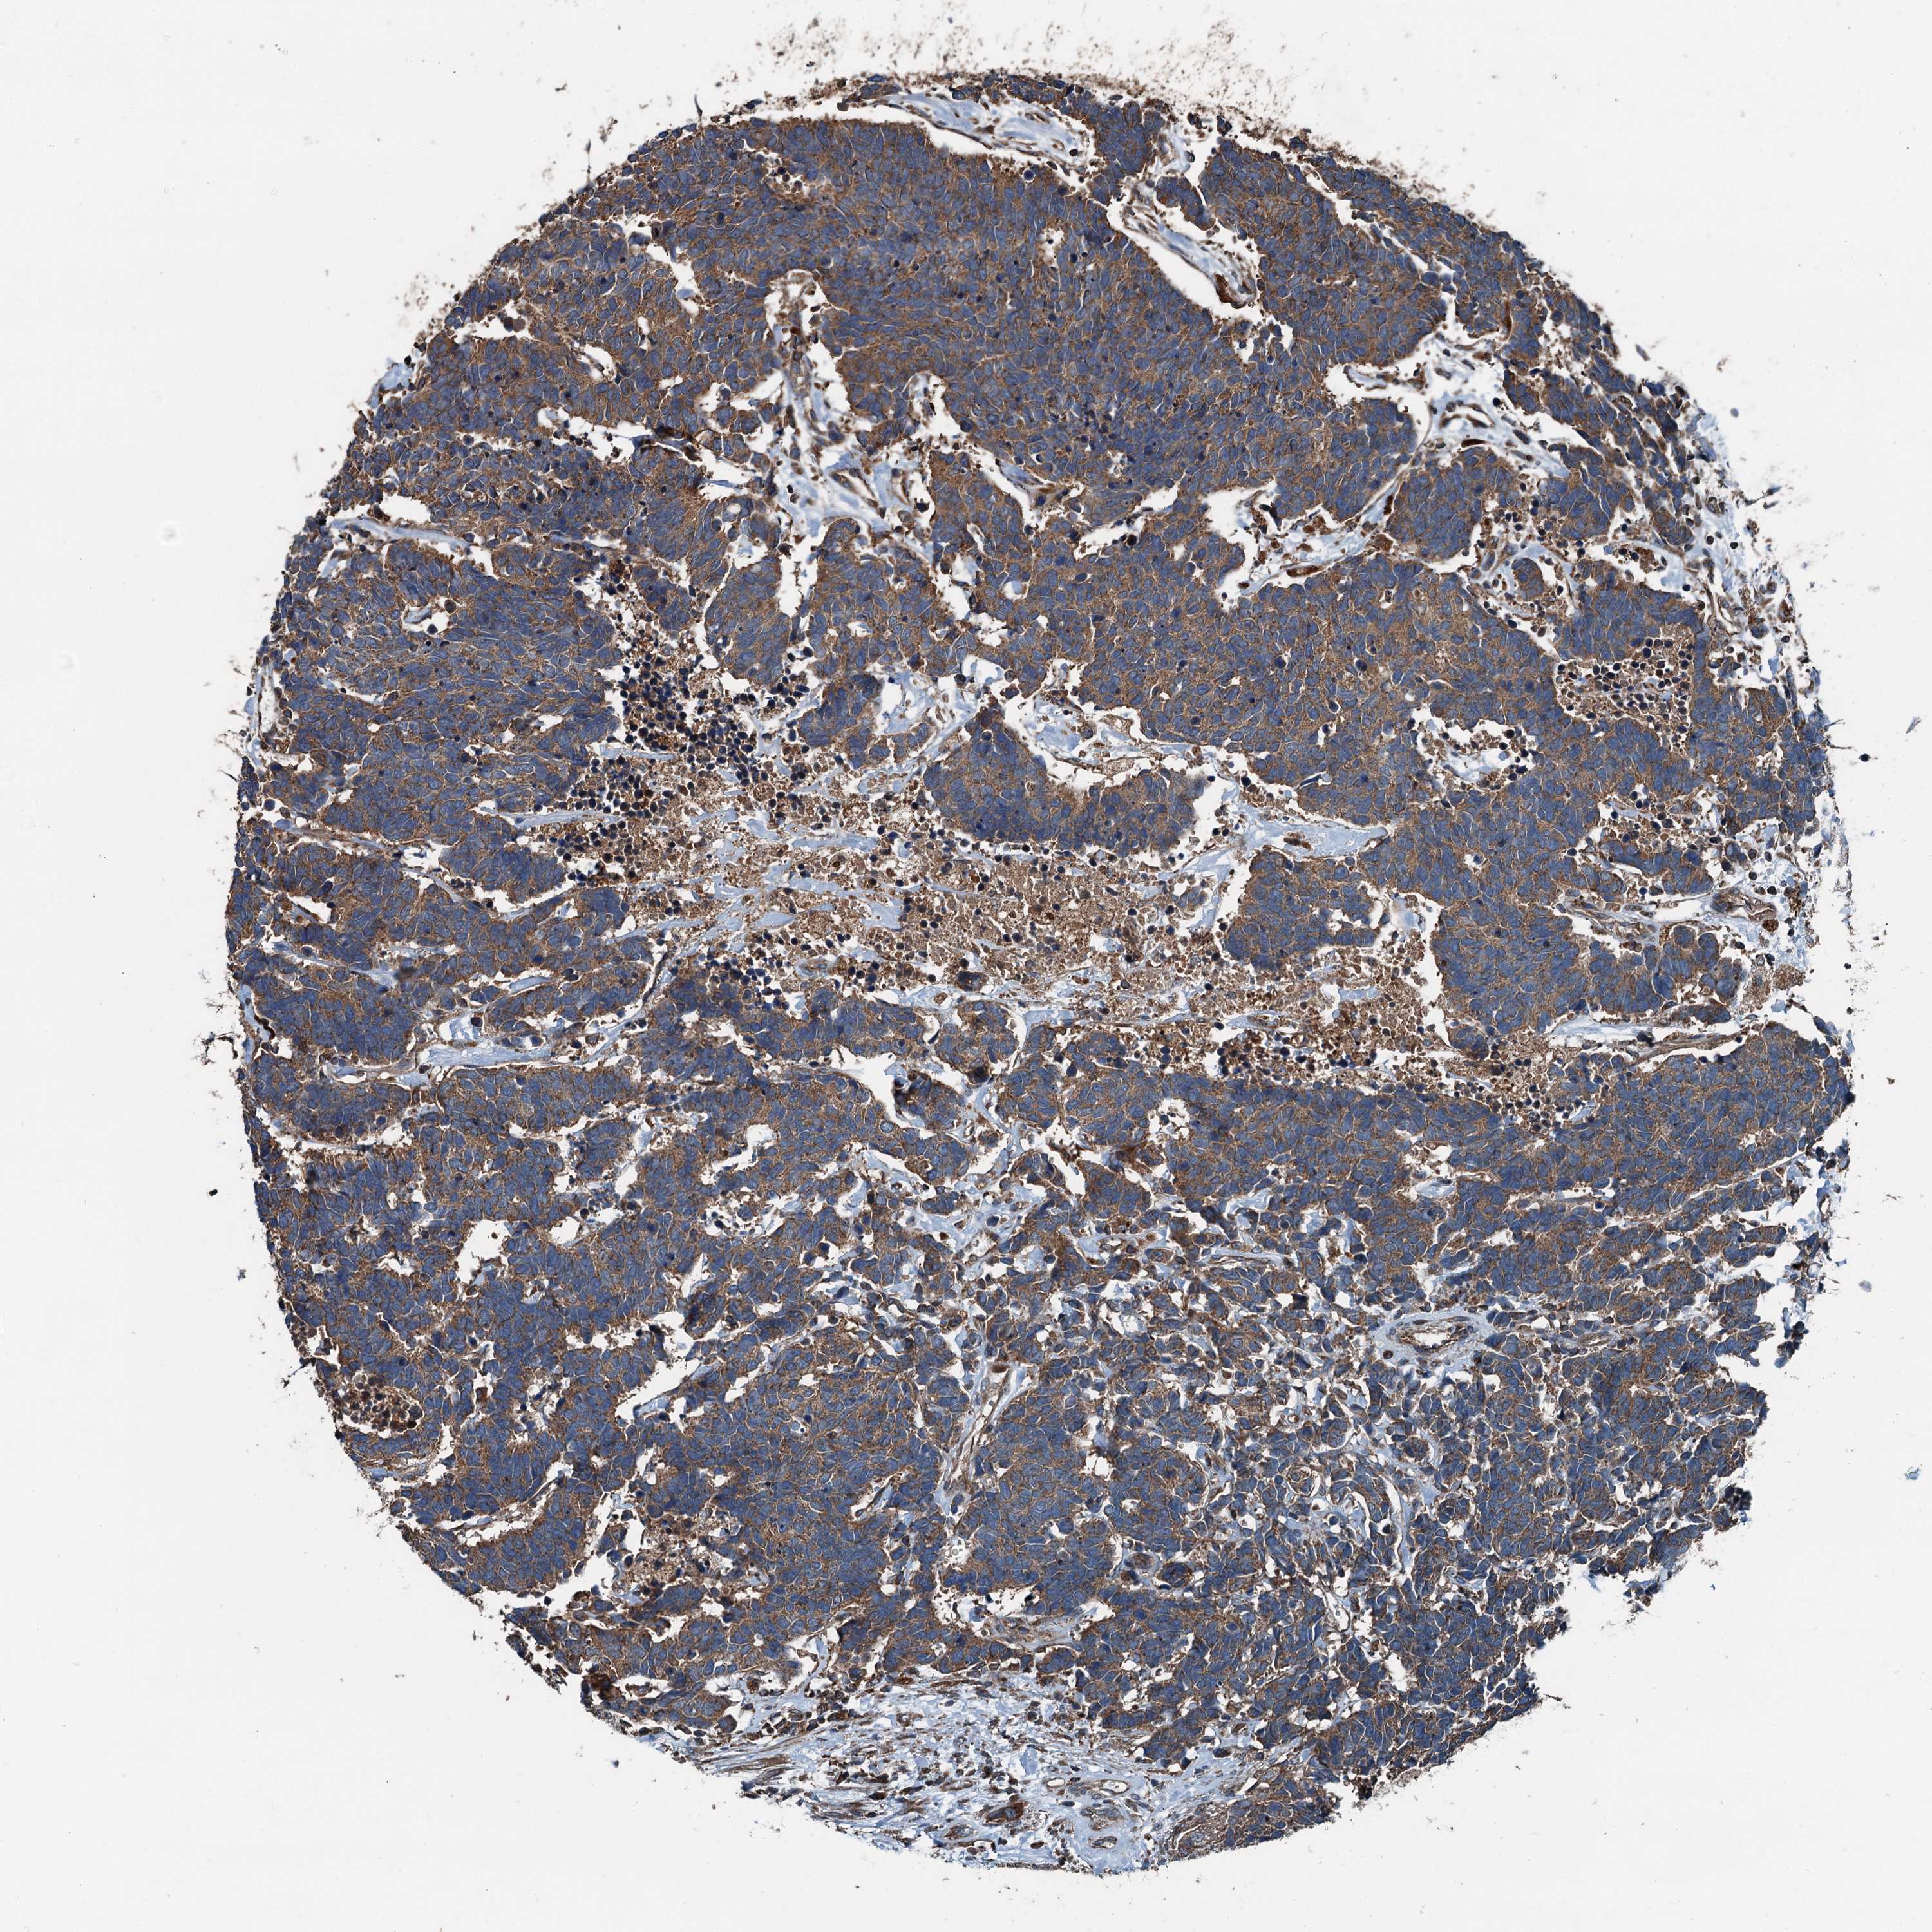

CARCINOID - Protein expressioni

A mouse-over function shows sample information and annotation data. Click on an image to view it in a full screen mode. Samples can be filtered based on level of antibody staining by selecting one or several of the following categories: high, medium, low and not detected. The assay and annotation is described here.

Antibody stainingi

Antibody staining in the annotated cell types in the current human tissue is reported as not detected, low, medium, or high, based on conventional immunohistochemistry profiling in selected tissues. This score is based on the combination of the staining intensity and fraction of stained cells.

Each image is clickable and will lead to virtual microscopy that enables deeper exploration of all samples and also displays staining intensity scores, fraction scores and subcellular localization as well as patient and tissue information for each sample.

Antibody HPA041227

Staining

High

Medium

Low

Not detected

Intensity

Strong

Moderate

Weak

Negative

Quantity

>75%

75%-25%

<25%

None

Location

Nuclear

Cytoplasmic/membranous

Cytoplasmic/membranous,nuclear

Carcinoid, malignant, NOS

Carcinoma, NOS